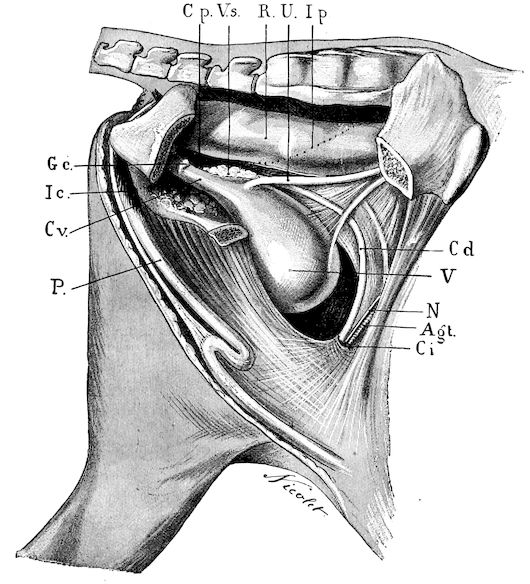

Fig. 8.—Transverse section through the middle region of the face in a pig suffering from osseous cachexia.

18In the final stages, the bones may be cut with a knife, and a time arrives when bony tissue seems completely to have disappeared; thus, as shown in Fig. 8 herewith, it was possible to cut the entire head of a pig into thin slices without the slightest difficulty. All parts of the head had been affected by the softening change.

From the chemical point of view, the diminution in mineral salts and in phosphate of calcium has long been recognised, but the degree of this change varies according to the phase. In human beings the proportions have been estimated as follows: Normal bone, 50 to 80 per cent. of phosphate of calcium; bone in persons suffering from osteomalacia, 5 to 20 per cent. of phosphate of calcium. The changes in the ossein have not been carefully studied. We only know that histologically the ossein becomes fibrillar, and that chemically it no longer retains its normal composition.